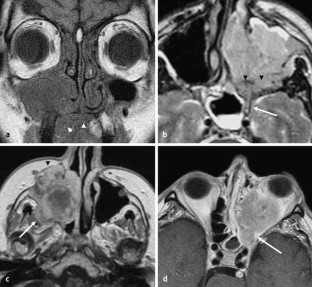

Abb. 3